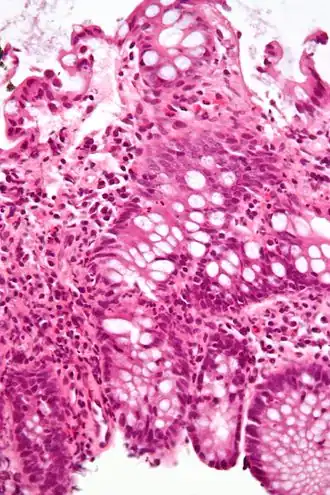

Une colite est une inflammation du côlon.

- Colite microscopique

- Colite collagène

- Colite lymphocytaire